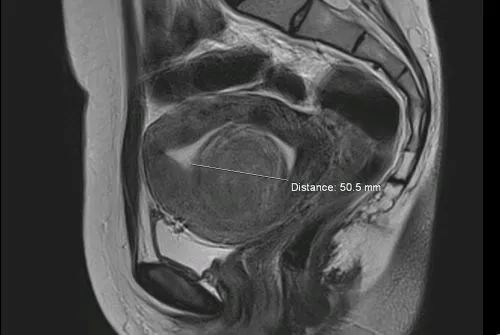

Podstawowym badaniem, które pozwala ocenić wielkość, lokalizację i strukturę guza, jest przezpochwowe USG (ultrasonografia transwaginalna). Jest to szybkie, bezbolesne i bardzo dokładne badanie, które pozwala ginekologowi na wstępną ocenę charakteru zmiany. Podczas USG lekarz zwróci uwagę na cechy guza, takie jak jego unaczynienie, jednorodność i obecność ewentualnych torbieli czy obszarów martwicy, które mogą sugerować złośliwy charakter.

Kiedy lekarz zleci rezonans magnetyczny (MRI) miednicy mniejszej?

W przypadkach niejednoznacznych wyników USG lub przy podejrzeniu zmian złośliwych, diagnostyka jest rozszerzana o rezonans magnetyczny (MRI) miednicy mniejszej. MRI to badanie o znacznie wyższej rozdzielczości, które pozwala na dokładniejszą ocenę struktury guza, jego relacji z sąsiednimi narządami oraz na wykrycie ewentualnych nacieków. Jest to szczególnie cenne narzędzie w różnicowaniu łagodnych mięśniaków od złośliwych mięsaków.